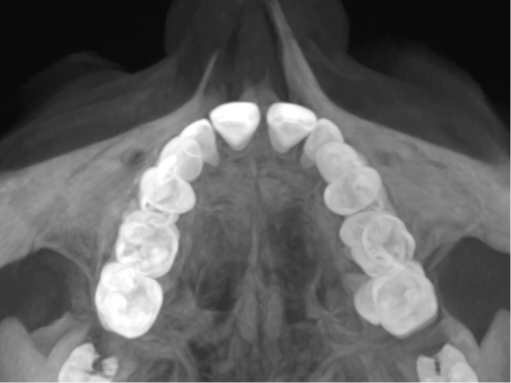

Invisalign Palatal Expander

Revisa tus casos de Invisalign Palatal Expander con nosotros y aprovéchate de un descuento del 50% hasta el día 30 de abril del Invisalign Palatal Expander

Este sistema, te permitirá diferenciarte y ser un referente de la ortodoncia invisible ¿te ayudamos?